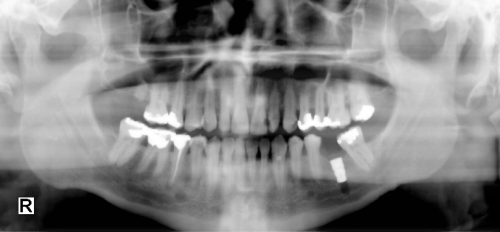

窗位(window level) 又称窗水平。是图像显示过程中代表图像灰阶的中心位置。

由于不同的组织的ct值不同,观察某一组织的结构细节时,应该以该组织的ct值为中心进行观察,此中心即窗位。

针对于ct系统的图片而言,一般来讲ctscaning之后dicom图片的黑白灰度级相对固定了,但具体去显示的时候,可根据窗位(window level)和窗宽(window width)的调节影响显示效果。

在固定窗宽下,窗位的变化也会影响图像ct值的变化范围,类似于坐标原点,表示ct值浮动的中心值。通常欲观察某组织的结构或者病变时,应以它的ct值作为其窗位。